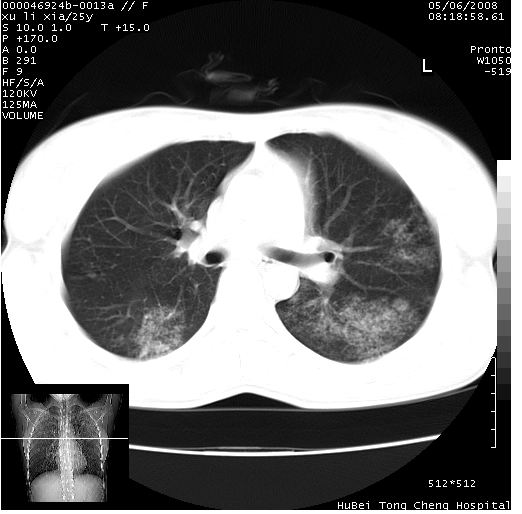

患者 女,25岁。因“左侧卵巢肿瘤”术前胸片偶然发现两肺病变。平素无明显不适,无呼吸系统症状及体征,无传染病史。

cr x线胸片提示:两肺感染性病变(结核可能性大)。

胸部ct轴位平扫(层厚10mm,螺距1.5,重建间隔10mm),图像如下:

(注:上级医院会诊胸部ct片——考虑为肺部真菌感染。)

病灶呈地图样分布于肺外围,与正常组织分界清晰+弥漫性磨玻璃影中见小叶间隔增厚呈碎石路样表现+年轻女性,无明显临床症状=肺泡蛋白沉积症?